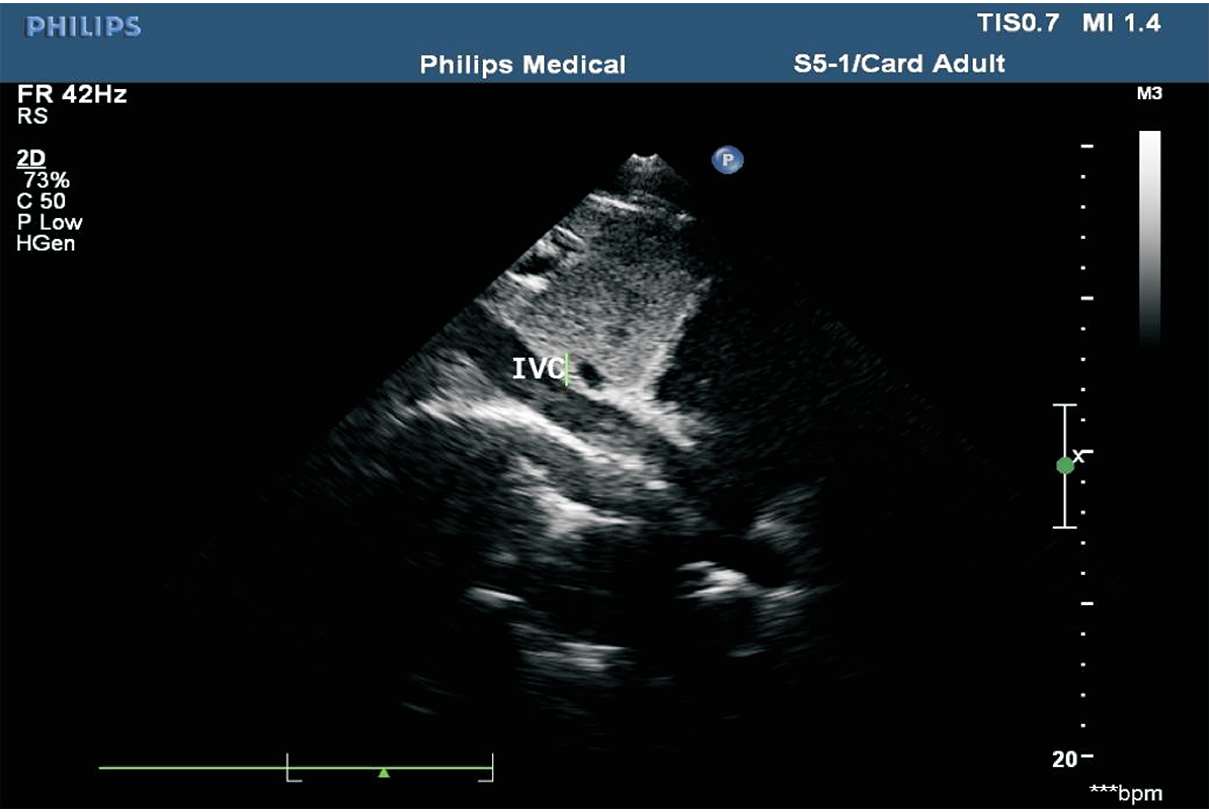

(3)下腔静脉的内径及塌陷率。在距右心房入口2 cm处测量下腔静脉内径。下腔静脉塌陷率=(下腔静脉最大内径-下腔静脉最小内径)/下腔静脉最大内径×100%。正常状态下,下腔静脉内径小于21 mm,塌陷率大于50%(见图1-43)。

图1-43 下腔静脉